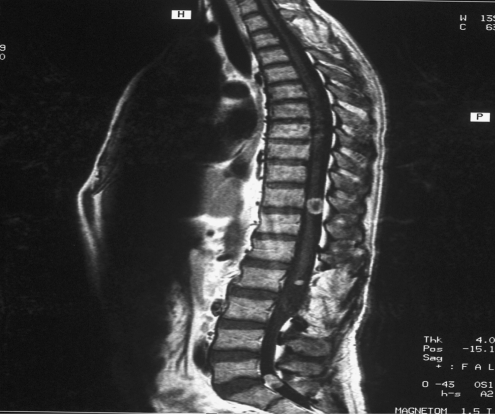

Fig. 2.

Thoracic Intradural lesion (case 1)

A 25-year-old gentleman underwent excision of three schwannomas over a span of 11 years. He first underwent surgery at age 14 for a neck swelling. Histopathology confirmed as schwannoma. He presented in 1998 with backache and radicular pain in his left leg with minimal weakness. MRI scan demonstrated well-defined intradural lesion at L2 enhancing with gadolinium. Cervical and thoracic MRI was normal. He underwent excision of the tumour and histopathology was confirmed as an schwannoma (Fig. 1). Following surgery his pain subsided and the power in the left leg improved to normal. Gadolinium MRI of the lumbar spine at 1 year showed total excision. Cervical, thoracic and cranial MRI were normal. Annual Brain stem auditory evoked potentials were also normal. In 2003 he had MRI of the thoracic spine due to pain in the midthoracic region. MRI scan demonstrated a small enhancing intradural lesion at T6 level. Since the lesion was small with no cord compression, surgery was not advised and he remained under review. In August 2004 he presented with right scapular pain radiating to the mid thoracic level and also pain in the right arm. MRI scan of the thoracic spine showed an increase in the size of the lesion (Fig. 2). He underwent total excision of the intradural lesion. Histopathology confirmed a schwannoma. He did not have any cutaneous markers for neurofibromatosis. Ophthalmologic examination was normal. There was no family history of neurofibromatosis. His cranial MRI was normal. BAEP were normal. NF2 mutation screening results are summarised in Table 2.